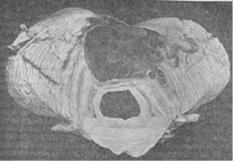

Менингиомы. [ 2]

а) конвекситальная полушария мозга; б) парасагиттальная в глубине межполушарной щели.

[2] Ангиоретикулема червя мозжечка.